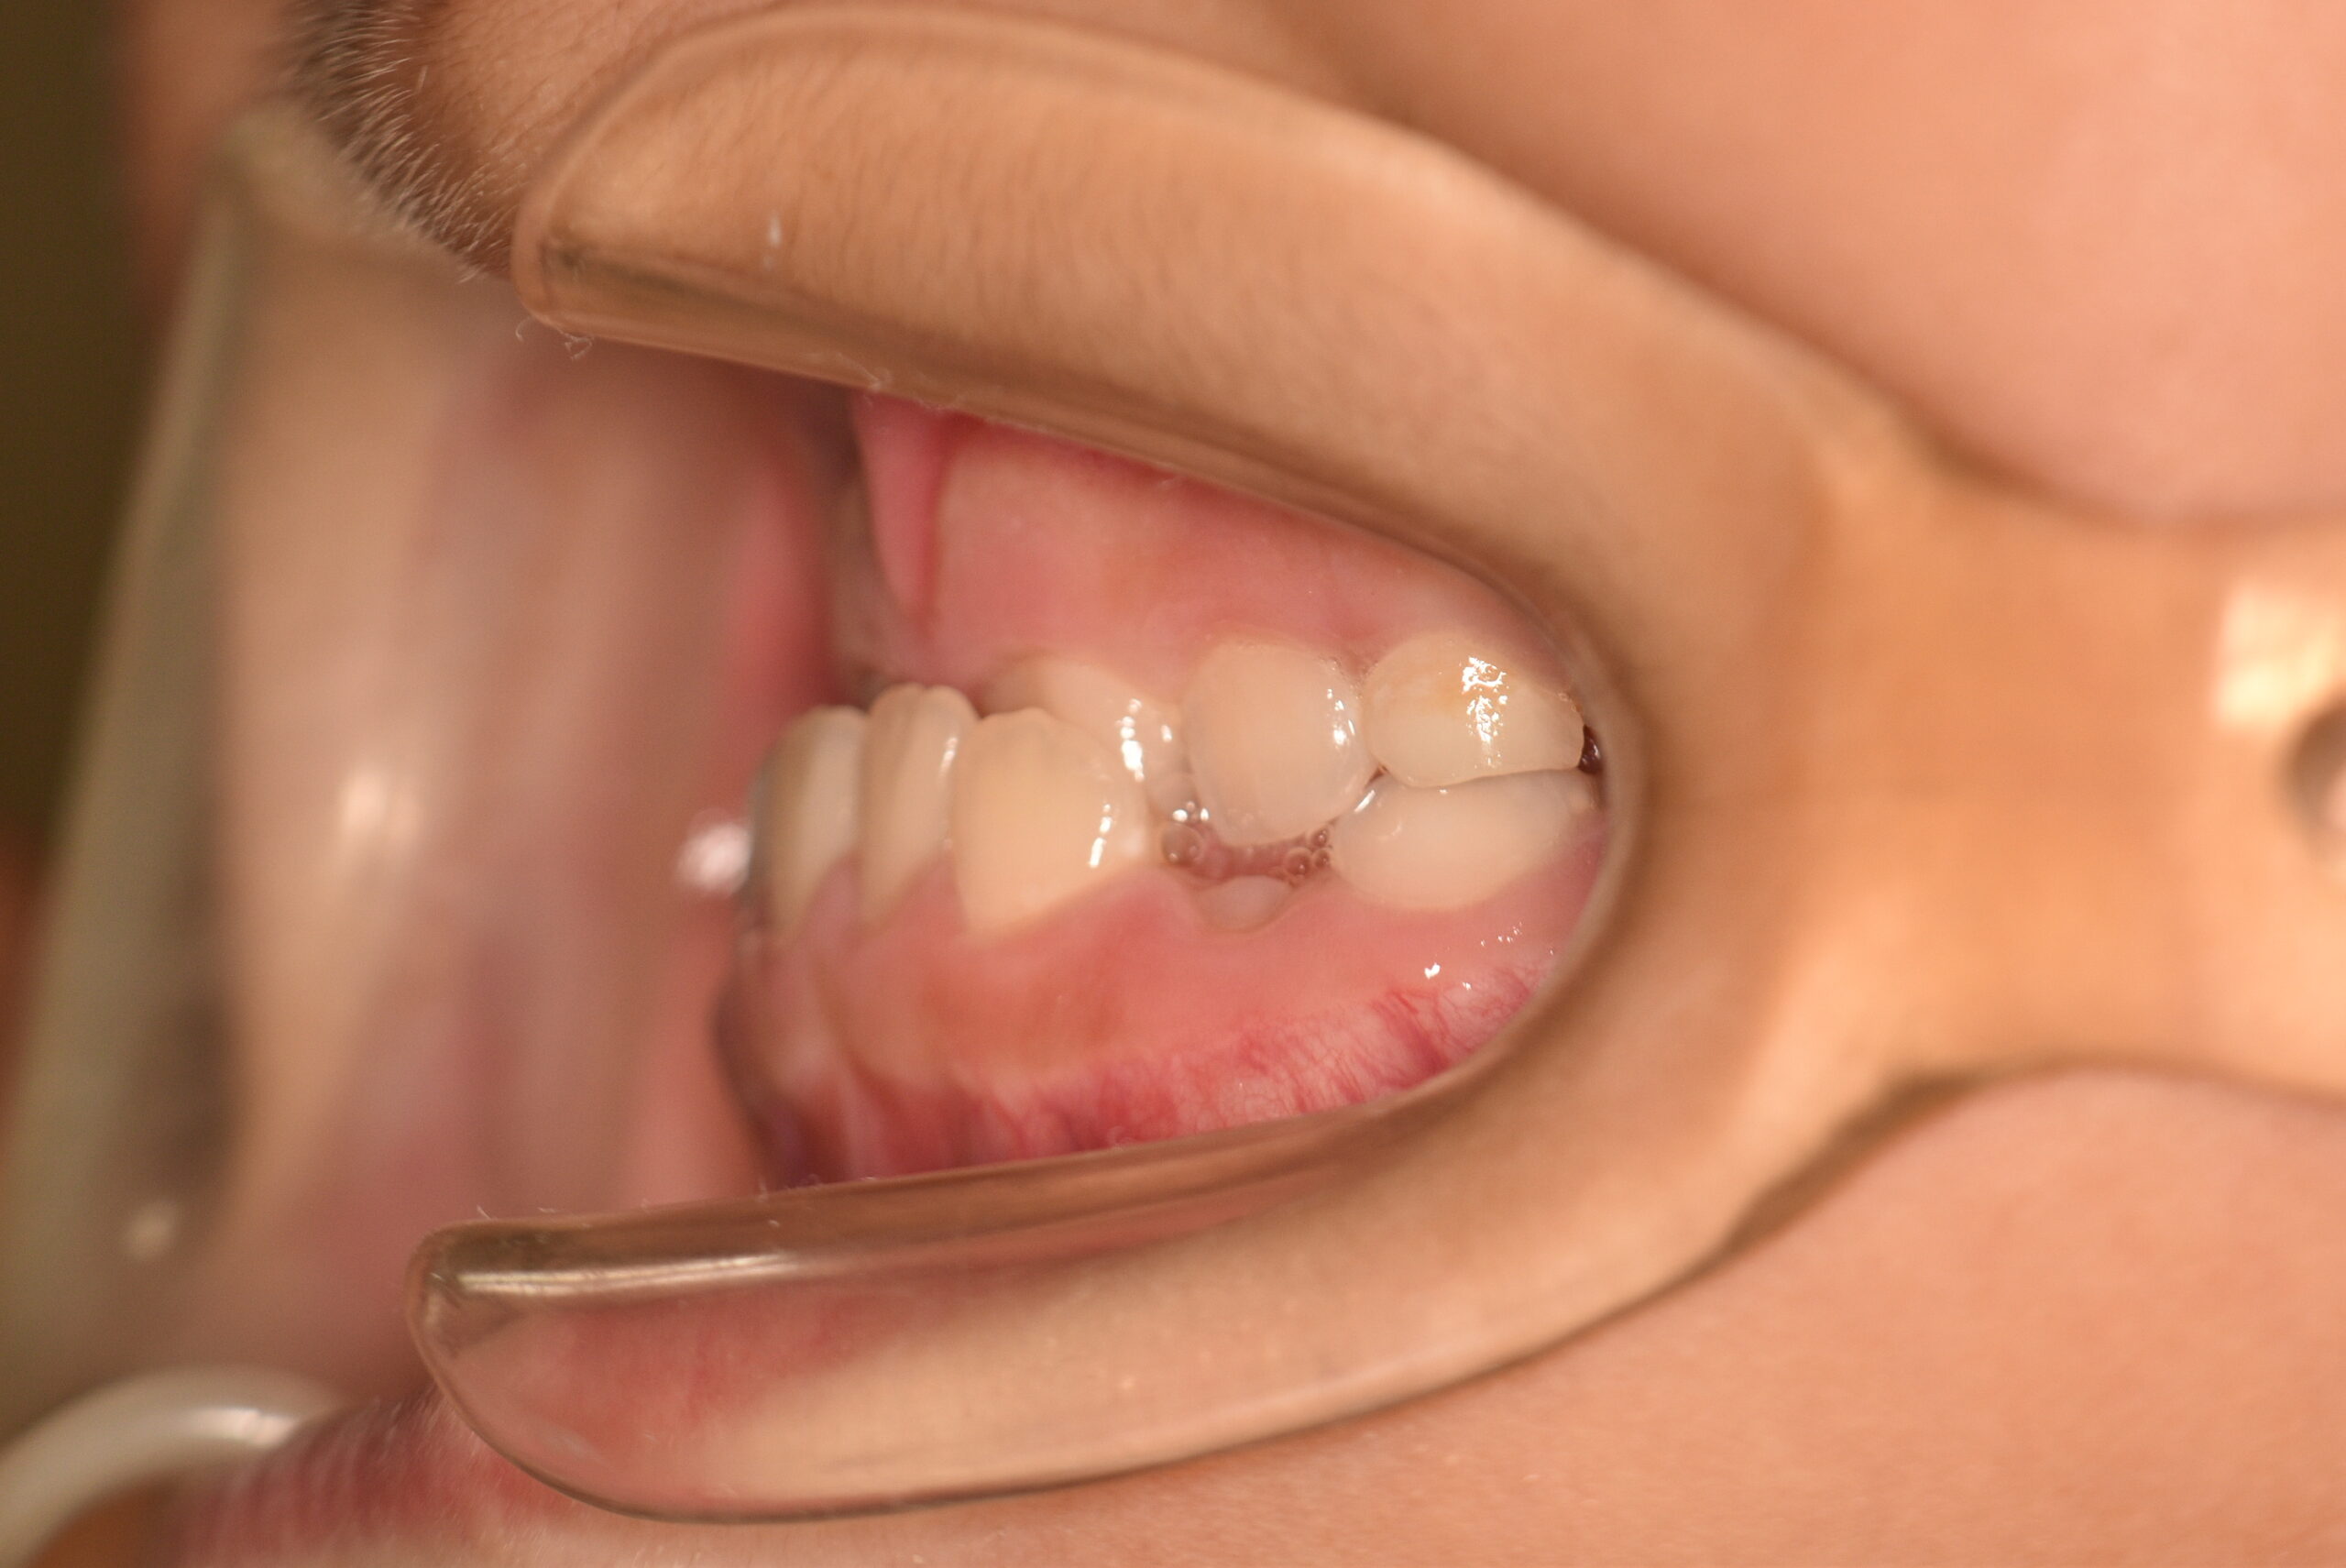

検査の結果、反対咬合を伴うアングルⅢ級不正咬合と診断しました。

治療としては、初期段階の治療として、リンガルアーチを使用して上顎前歯部を前方へ移動させ、反対咬合の改善を行いました。また、機能的矯正装置で鼻呼吸の獲得と舌の位置や口唇の閉鎖といった筋機能習癖の改善を行いました。

永久歯列に交換後、非抜歯の上、セルフライゲーションブラケット装置(デーモンシステム)で歯の配列を行いました。